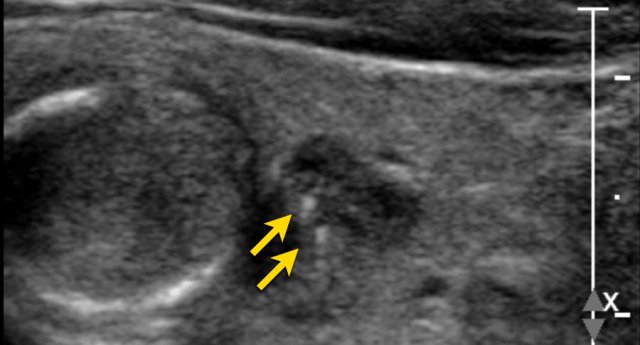

Echogenic foci

Study the image and score for TI-RADS.

Scroll the image for the TI-RADS score.

Then continue reading.

Only 1 point for the macro calcification.

This is a TI-RADS 5 lesion mainly due to the very hypoechoic echogenicity.

Maybe the lesion is also taller than wide, which would mean 3 extra points.